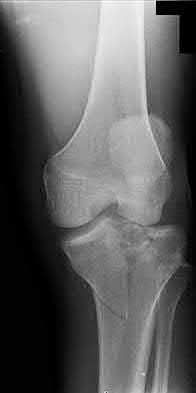

2. # A 35-year-old woman is involved in a head-on collision while driving. Initial radiographs are shown in Figures 8a and 8b. Injury to what vessel increases the risk for osteonecrosis of the injured bone?

5. Artery of the tarsal sinus Corrent answer: 4

The patient has a Hawkins type III talar neck fracture-dislocation with a risk of osteonecrosis ranging from 69% to 100%. Anatomic studies have shown that the artery of the tarsal canal supplies the lateral two thirds of the talar body.

The other vessels listed provide no significant contribution to the talus.